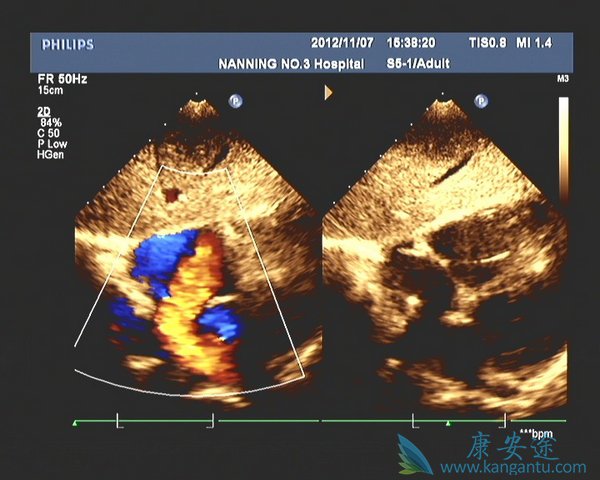

4. 糖尿病性心脏病:2型糖尿病性心脏病的筛查最常做的是心电图和心脏彩超。心电图可以反映心脏有无缺血及心律失常的情况。心脏彩超可以及早发现心脏结构和心功能是否存在异常。通过这些检查,可以排查冠心病、心肌梗死等心血管并发症。许多糖尿病患者由于感觉神经受损,往往表现为无症状性心肌缺血,即便是发生心绞痛、心肌梗塞,也不会出现疼痛等警示症状,因此十分危险。建议初次确诊的糖尿病患者一定要做心电图检查,每三个月到半年复查一次。